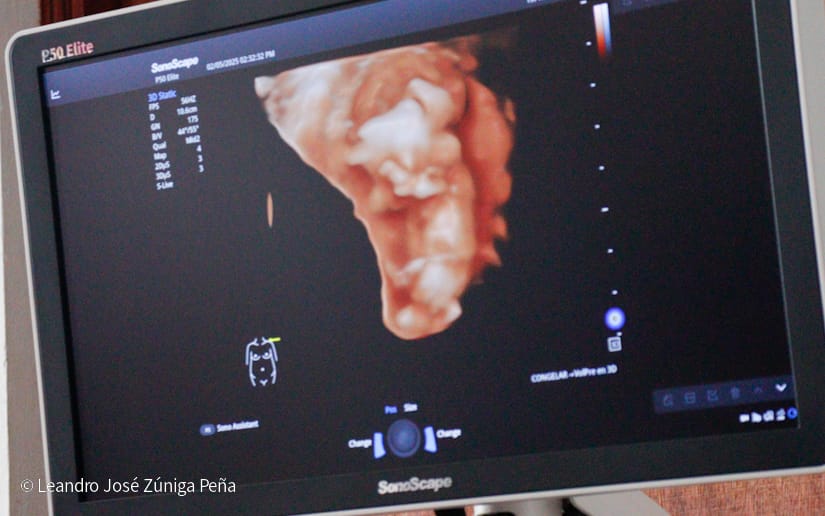

“Con estos ultrasonidos, que son de alta tecnología en el país, estamos completando 32 equipos de ultrasonido que están ubicados en las diferentes unidades de salud. Estos últimos 6 equipos nos van a permitir hacer diagnóstico de manera preventiva a la mujer embarazada, tenemos recursos humanos calificados, médicos especialistas formados por nuestro gobierno, en nuestro país, que tienen todos los conocimientos necesarios para poder hacer diagnóstico de anomalías congénitas, diagnóstico prenatal de alteraciones en la embarazada y en el feto y poder hacer prevención de la preclancia, el parto prematuro, la restricción del crecimiento fetal o bajo peso, que son morbilidades que afectan a nuestras embarazadas y a nuestro recién nacido, de igual manera, la tecnología volumétrica que se ha adquirido en estos equipos como el 3D y el 4D permite obtener mejores imágenes de anomalías congénitas para que estas pacientes que son captadas en estas unidades puedan ser referidas al Bertha Calderón”, explicó el especialista.